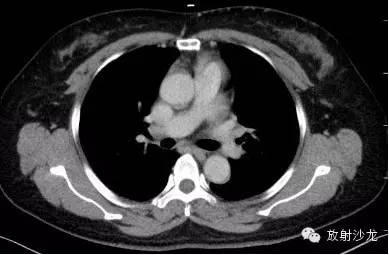

第三例:

51岁男性,体检发现肺门、纵隔、腹腔淋巴结肿大,CT拟诊结节病,后于北京协和医院确诊。

第1—3图显示Garland三联征。第4图显示腹腔淋巴结肿大。